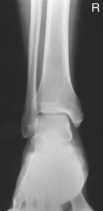

• Supine, or seated on table, with leg extended and centered to CR and midline of table or IR

• Rotate leg slightly inward as needed to place knee and leg into a true AP. Center IR to CR.